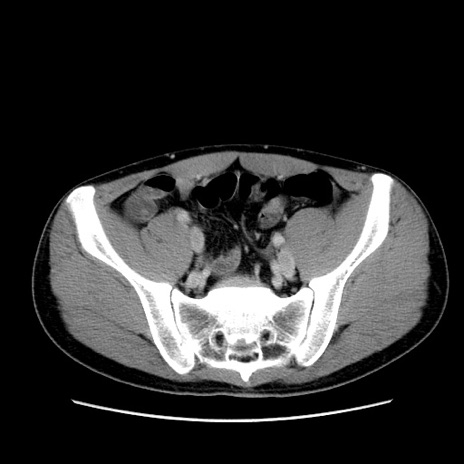

症例36(横断像)

【症例】20歳代 男性

【主訴】心窩部痛

【現病歴】今朝より上腹部痛あり。一旦軽快していたが再度出現したため救急要請。昨日夕に白身の魚を含む刺身を食べた。

【身体所見】BP 136/89mmHg、HR 74/min、BT 37.0℃、腹部:膨満、軟、心窩部に圧痛あり。反跳痛なし、筋性防御なし、腸雑音やや亢進あり。

【データ】WBC 17700、CRP 0.48